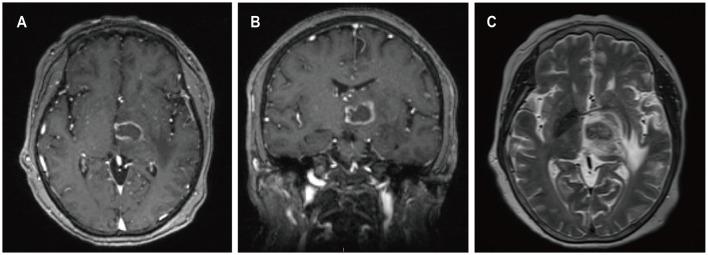

Four patients had previously received a kidney transplant, one had undergone allogeneic HSCT. The median time from the last transplant surgery to the diagnosis of PCNS-PTLD differs between kidney transplant (21.5 years) and allogeneic HSCT (9 months). Common symptoms included motor weakness ( = 4), headache ( = 2), confusion ( = 2), and nausea ( = 2), with ring-enhancing ( = 5), typically solitary ( = 3) and supratentorial ( = 3) lesions on imaging. Diagnosis involved robot-assisted stereotactic brain biopsy ( = 4) or craniotomy ( = 1), all showing Epstein-Barr virus and CD20 positivity. Most cases ( = 4) were monomorphic diffuse large B-cell lymphoma. Treatment included rituximab ( = 3), surgical resection ( = 2), zanubrutinib ( = 1), whole-brain radiation ( = 1), and methotrexate ( = 1). At the last follow-up, the median duration of follow-up for all patients was 19 months. During this time, 3 patients had died and 2 patients were still alive.

In patients with a history of kidney transplantation or allogeneic HSCT who are on long-term immunosuppressive therapy, any neurological symptoms, particularly the presence of supratentorial ring-enhancing masses in the brain on imaging, whether solitary or multiple, should raise high suspicion for this disease, warranting a timely brain biopsy. Additionally, we found that besides reducing immunosuppressants, zanubrutinib may be a potential, safe, and effective treatment for this condition. Moreover, post-surgical administration of rituximab in conjunction with whole-brain radiotherapy also appears to be a potentially safe and effective approach.

4例患者曾接受肾移植,1例接受异基因HSCT。从最后一次移植手术到诊断为PCNS-PTLD的中位时间在肾移植(21.5年)和异基因HSCT(9个月)之间有所不同。常见症状包括运动无力(n = 4)、头痛(n = 2)、意识模糊(n = 2)和恶心(n = 2),影像学检查显示有环形强化(n = 5),通常为单发(n = 3)且位于幕上(n = 3)病变。诊断采用机器人辅助立体定向脑活检(n = 4)或开颅手术(n = 1),所有结果均显示爱泼斯坦-巴尔病毒和CD20阳性。大多数病例(n = 4)为单形性弥漫性大B细胞淋巴瘤。治疗方法包括利妥昔单抗(n = 3)、手术切除(n = 2)、泽布替尼(n = 1)、全脑放疗(n = 1)和甲氨蝶呤(n = 1)。在最后一次随访时,所有患者的中位随访时间为19个月。在此期间,3例患者死亡,2例患者仍存活。

对于有肾移植或异基因HSCT病史且长期接受免疫抑制治疗的患者,任何神经系统症状,特别是影像学检查显示脑内幕上有环形强化肿块,无论单发或多发,都应高度怀疑此病,需及时进行脑活检。此外,我们发现除了减少免疫抑制剂外,泽布替尼可能是治疗这种疾病的一种潜在、安全且有效的方法。此外,术后给予利妥昔单抗联合全脑放疗似乎也是一种潜在安全有效的方法。